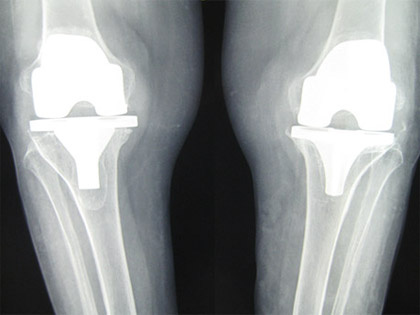

The company ORTHOPEDIC NIKIFOROV was founded in 1998 by the candidate of medical sciences. doctor of orthopedic-traumatologist of the highest category Nikiforov IA Owing to high professionalism and results of work, ORTONIC has gained well-deserved reputation and reputation among colleagues and population of Dnepropetrovsk region and CIS countries (Russia, Moldova, Armenia, etc.). The principle of the enterprise is NO IMPOSSIBLE, it is based on knowledge, experience and active implementation of modern technologies in orthopedics and traumatology. Conservative methods of treatment include individual selection of medicines, therapeutic blockades, manual therapy, massage, physiotherapy (vibration table, magnetotherapy, bioptron, electromyostimulation, etc.), rehabilitation with the suggestion of the necessary concomitant devices and means for the fastest recovery (corsets, bandages, various joint fixators, crutches, walking sticks, etc.). Various minor invasive interventions (chymonucleolysis, vertebroplasty, kyphoplasty, percutaneous nucleoplasty using cold plasma) that are performed on an outpatient basis are successfully used to treat problems associated with spine pathology. The latest modern treatment methods introduced in our company are endoscopic operations using the TYSSES technique of Joimax (Germany) with intervertebral hernias, stenosis and other pathologies of the spine, which allow to avoid complications occurring during open operations and the accompanying general anesthesia. We have many years of successful experience in traditional and modern minimally invasive endoprosthetics of large and small joints, which remains the main direction of our activity. Our company is the exclusive representative of the German company IO International Orthopaedics Holding GmbH, which based on the already known prostheses, its ideas and technological capabilities, has developed and implemented a new concept in hip replacement - an artificial joint prosthesis (ICON). We assist interested colleagues in training the operative technique for installing an artificial joint prosthesis - ICON, both in the workplace and in Germany. For 20 years we have been successfully cooperating with Sanitatshaus Gerd Klinz ortho team, an enterprise that for 20 years has been one of the leading places in Germany for the production of functional prostheses of the upper and lower limbs, as well as cosmetic prostheses of limbs and other body parts (nose, ears, eyeballs, fingers). We have an atmosphere of friendliness and human participation. Politeness, benevolence, the desire to understand and help is the basis of our attitude towards patients. We are always glad to see you and will do our best to make you feel great! We are waiting for you at: Ukraine, Dnepr, Gagarin Ave., 13 (under reconstruction) on all questions to address: tel .: +38 (050) 488-88-92 E-mail: orthonik.ukr@gmail.com Germany, Spine Nano Klinik, Zeppelinstr. 21, Potsdam Tel. +4901801121919 E-mail: kmw.nikiforov@hotmail.de